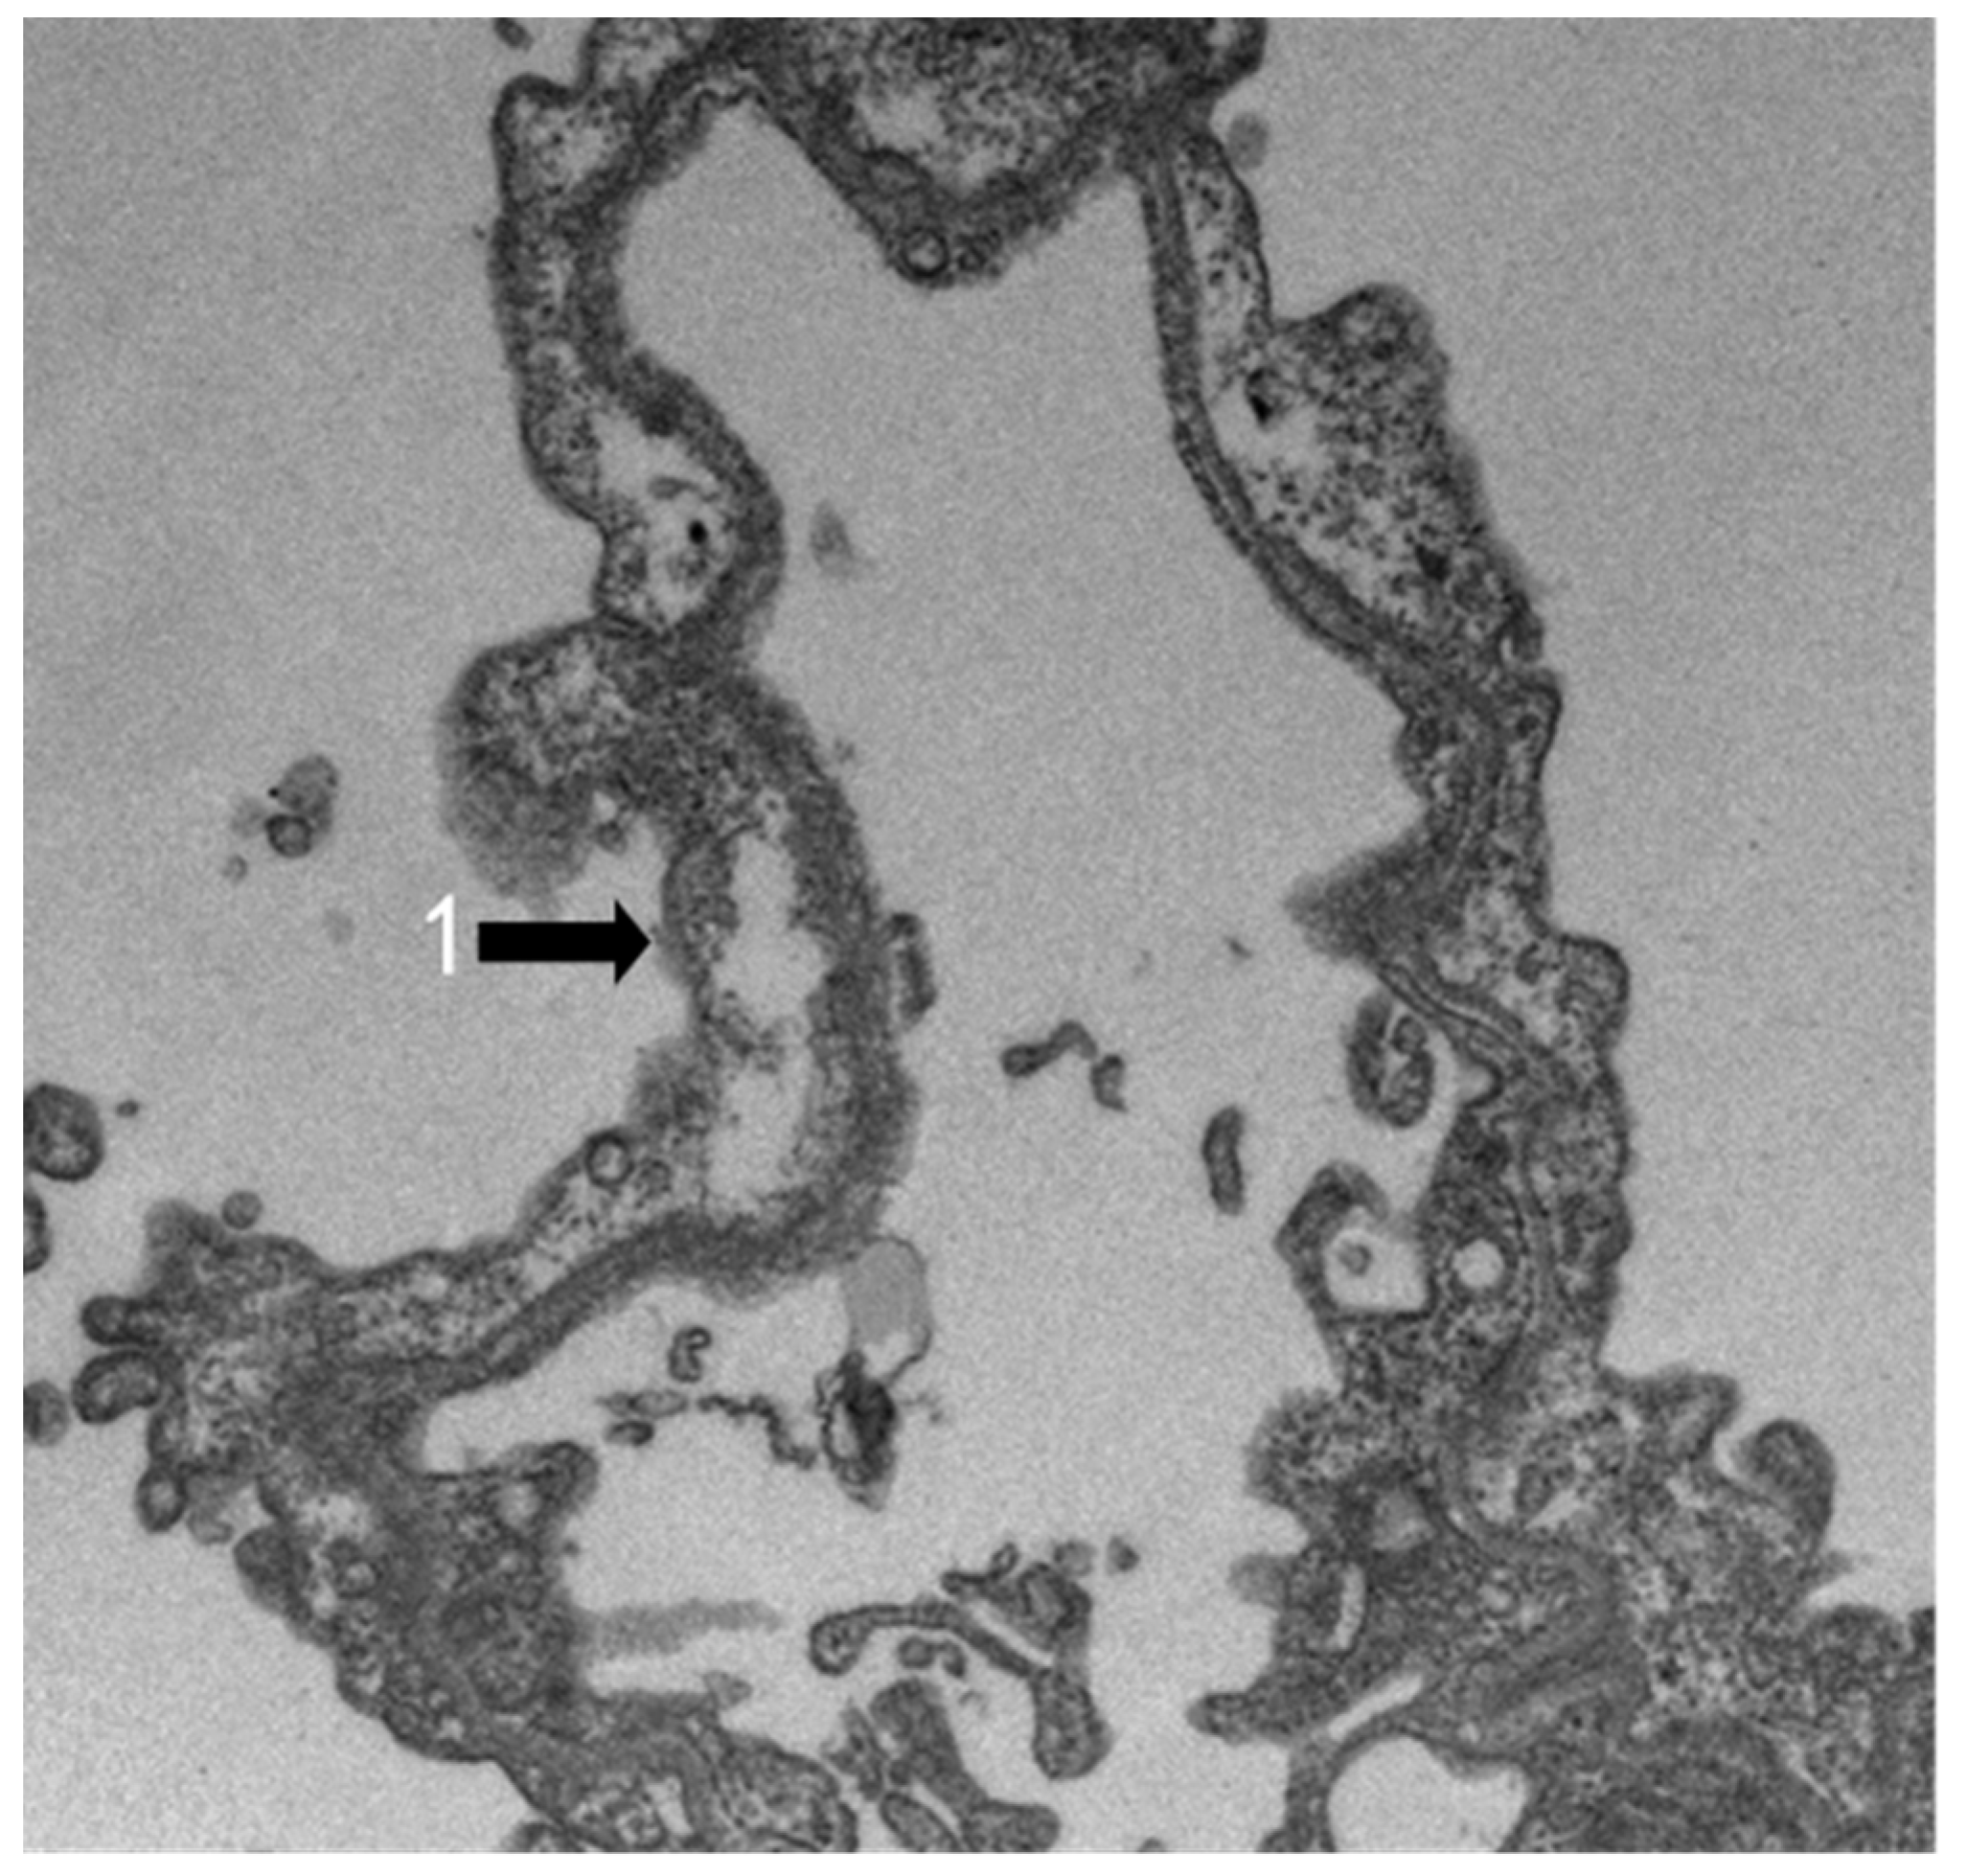

3.2. TEM Observation